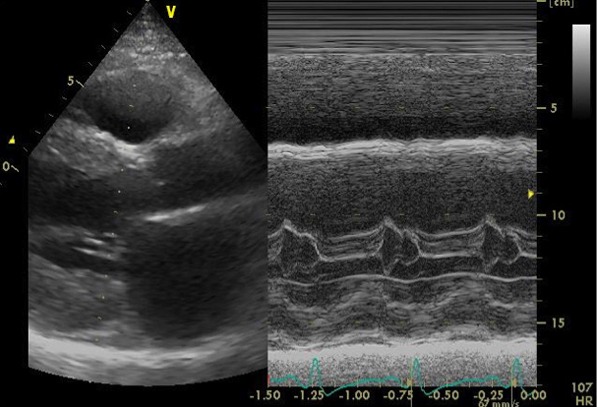

心エコー検査では、弁機能に異常なく、心嚢液の貯留はない。左房径(64mm)と左室径(60mm)は著明に拡張、左室は瀰漫性に壁運動の低下(EF=20%)。左室壁は中隔厚(18mm )、左室後壁厚(21mm)と共に肥厚しており、長年の左室圧負荷に加え、左室の収縮不全を認めることから、高血圧性心疾患に加え何らかの心筋疾患の可能性も否定できない。

心エコー画像1

心エコー画像2

心エコー画像3